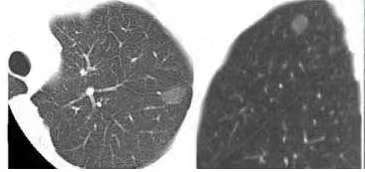

首先要明确:80%以上的肺结节是良性的,比如炎症、结核留下的疤痕,或是肺泡上皮增生形成的良性结节。只有当结节出现“高危信号”时,才需要警惕——比如直径超过8毫米、边界模糊、有毛刺或胸膜牵拉征,或是磨玻璃结节中实性成分占比增加。这时医生会建议进一步检查,而手术往往是确诊与治疗的双重选择。

很多人怕手术,核心是担心“切多了伤肺,切少了漏癌”。这就不得不提肺结节手术的第一个关键环节——术前精准定位,这是避免手术“走弯路”的核心。肺像不停起伏的“海绵”,直径小于1厘米的微小结节,就像藏在棉絮里的小芝麻。胸腔镜手术中,医生通过小孔操作,单靠视觉很难锁定病灶。这时术前穿刺定位就成了“导航仪”。

哪些情况能做亚肺叶切除?医学研究给出了明确答案:直径≤2厘米的早期肺癌,尤其是以磨玻璃成分为主的结节,亚肺叶切除的5年生存率与肺叶切除基本一致。比如CTR值(肿瘤实性成分占比)≤0.25的磨玻璃结节,术后10年生存率高达94%,且几乎无复发,完全没必要切除整个肺叶。对于肺功能较差的老年患者,亚肺叶切除更是保障生活质量的关键。